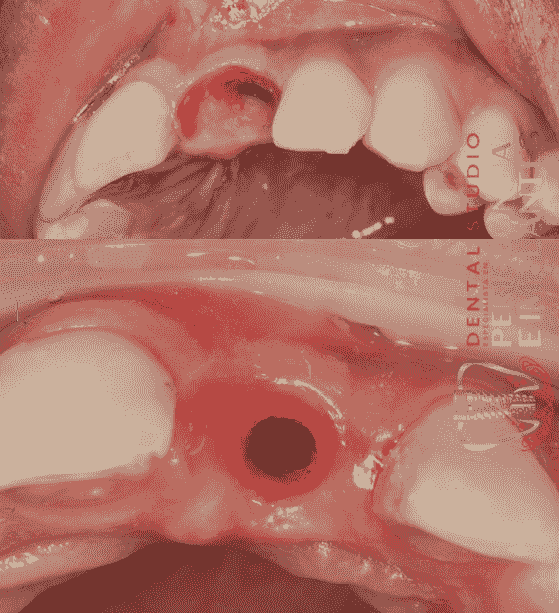

Implante Inmediato pos exodoncia de diente fracturado (central superior izquierdo)

Paciente con fractura del central superio izquierdo; se le realiza la exodoncia mínimamente traumática, posterior a ello se coloca un implante con la asistencia de una guía quirúrgica y se realiza carga inmediata sin contacto oclusal.